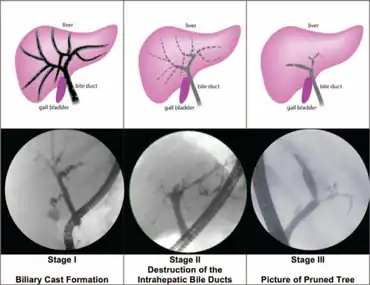

| Cholangiographic findings of SCC-CIP. SSC-CIP = secondary sclerosing cholangitis in critically ill individuals | |